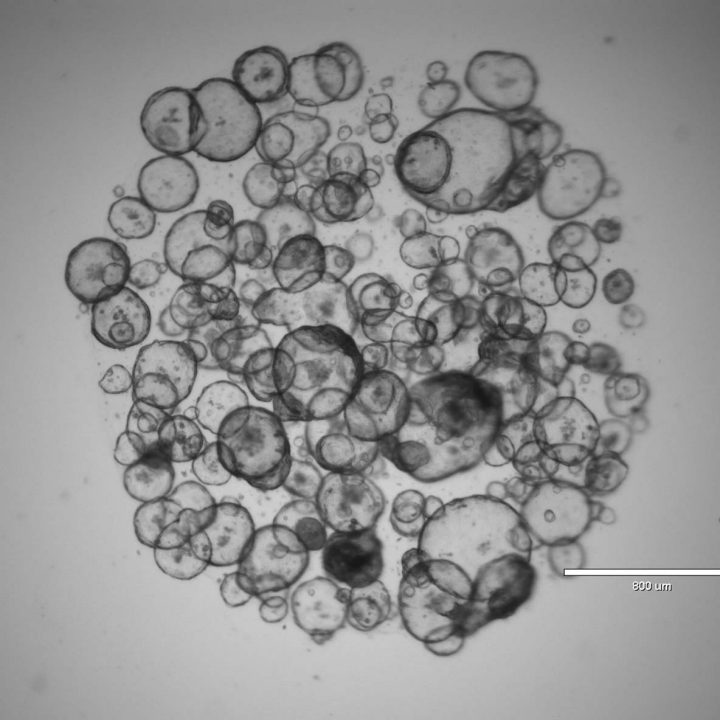

3D Cell Culture Primer Freezing, Culturing, and Measuring Organoids What Happens If Primer Freezes That means when it thaws, the consistency and texture may be ruined. when paint freezes, it can affect the emulsion of the paint. what happens if paint gets frozen? That’s because the water content has a freezing point at around 32°f (0°c). paint can freeze, depending on the type of paint. freezing affects the paint consistency. What Happens If Primer Freezes.